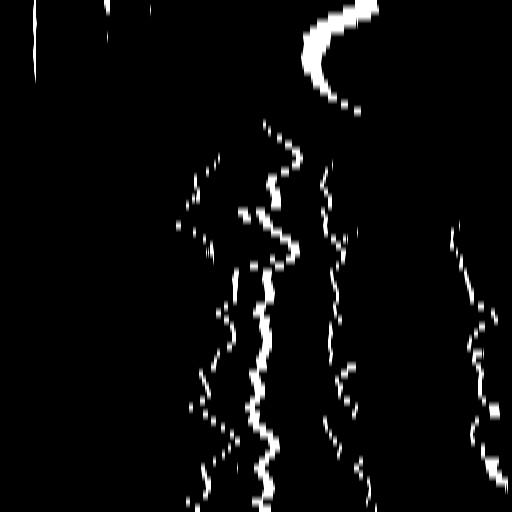

7 Temporal Coherency

Our method takes an entire X-ray video as input, thus producing segmentation results with better temporal coherency. Temporal coherency is essential for making medical diagnoses, especially when dealing with blood flow in vessels. Therefore, we conduct visual comparisons between our method and other compared methods by slicing horizontally or vertically and stacking the segmentation results. The results in Fig. 14 show our method strikes a better balance between segmentation accuracy and temporal coherency. While other baseline methods either produce false segmentation results or do not maintain consistent prediction along the temporal dimension.